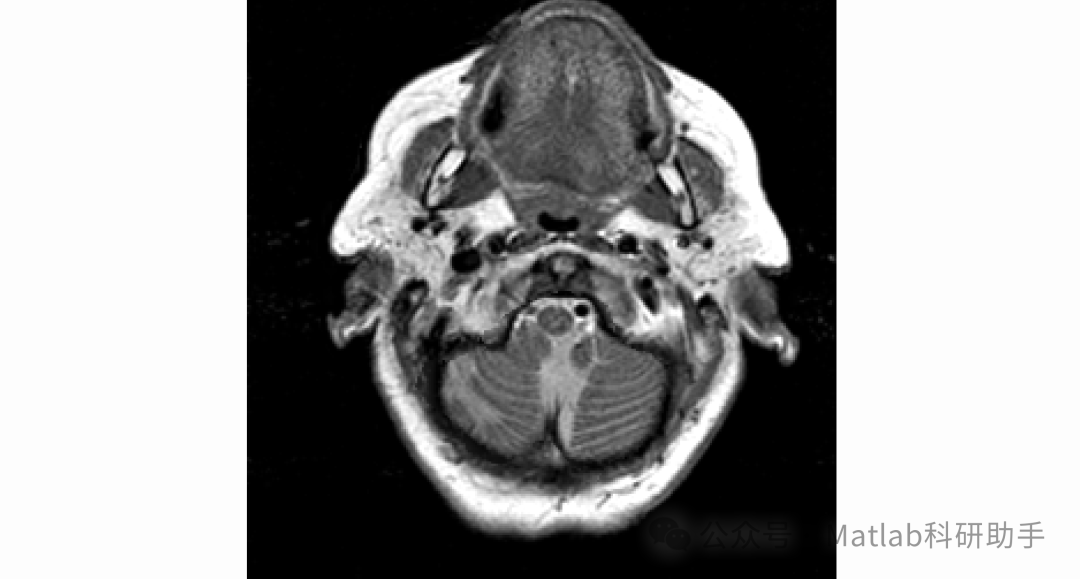

在现代医学诊断领域,医学影像技术扮演着不可或缺的角色。不同模态的医学图像能够提供人体组织和器官的不同信息,例如 CT 图像具有较高的空间分辨率,能够清晰地显示骨骼等高密度组织的结构;MRI 图像则对软组织的分辨能力较强,可准确呈现脑部、肝脏等软组织的病变情况。然而,单一模态的医学图像往往存在信息局限性,难以全面反映人体的生理和病理状态。

多模态医学图像融合技术应运而生,其旨在将不同模态医学图像中的有用信息进行整合,生成一幅包含更丰富、更全面信息的融合图像,为医生的诊断和治疗方案制定提供更有力的支持。例如,在肿瘤诊断中,将 PET 图像(可显示肿瘤代谢活性)与 CT 图像(可显示肿瘤位置和形态)融合,能够帮助医生更准确地确定肿瘤的范围和性质,从而制定更精准的治疗计划。

当前,多模态医学图像融合技术已成为医学图像处理领域的研究热点之一。但在实际应用中,现有融合方法仍存在一些问题,如融合图像可能出现细节丢失、边缘模糊、伪影等现象,影响了图像的质量和诊断价值。因此,研究更加有效的多模态医学图像融合方法具有重要的理论意义和实际应用价值。

本文针对多模态医学图像融合中存在的细节丢失、边缘模糊等问题,提出了一种基于联合双边滤波和局部梯度能量的多模态医学图像融合方法。通过对源图像进行联合双边滤波预处理,有效地去除了图像噪声,保留了图像的边缘和细节信息;利用局部梯度能量作为融合决策依据,确保了融合图像能够保留更多的细节信息;最后通过直方图均衡化和边缘增强等后处理操作,进一步改善了融合图像的质量。

实验结果表明,该方法在主观评价和客观评价方面均优于传统的图像融合方法,能够生成高质量的多模态医学图像融合结果,为医生的诊断和治疗提供了更有力的支持。